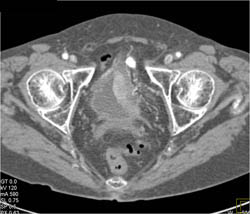

Bladder Cancer